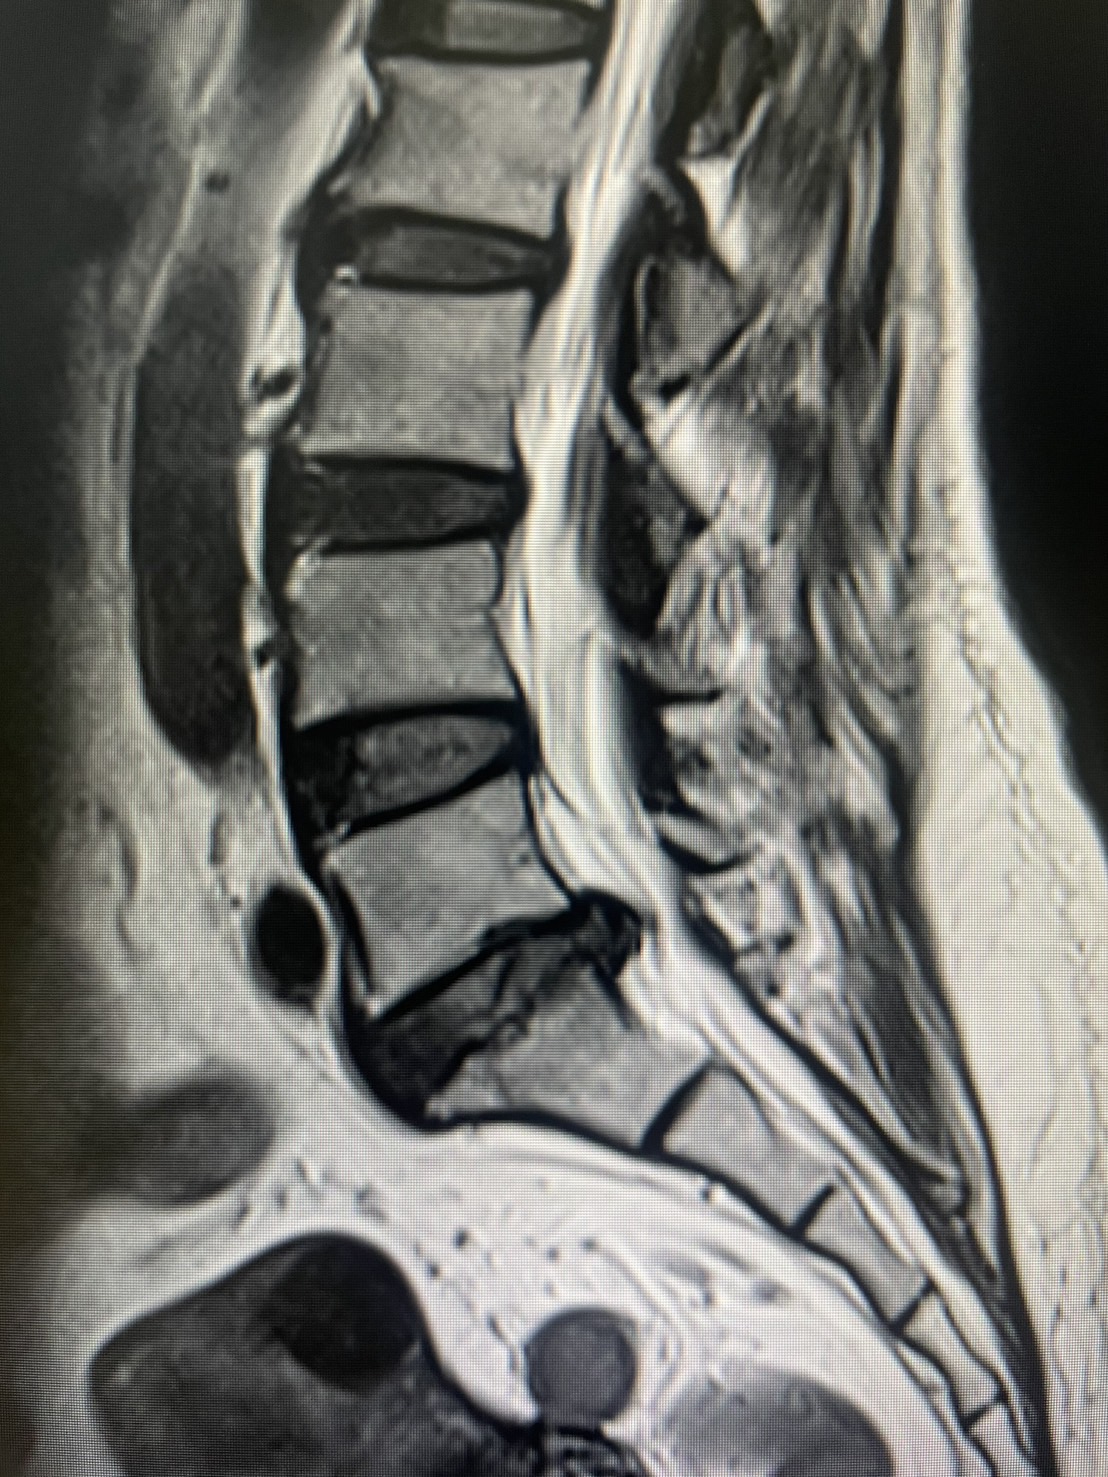

การวินิจฉัย สามารถทำได้โดยการตรวจภาพถ่ายเอกซเรย์คลื่นแม่เหล็กไฟฟ้า หรือ MRI